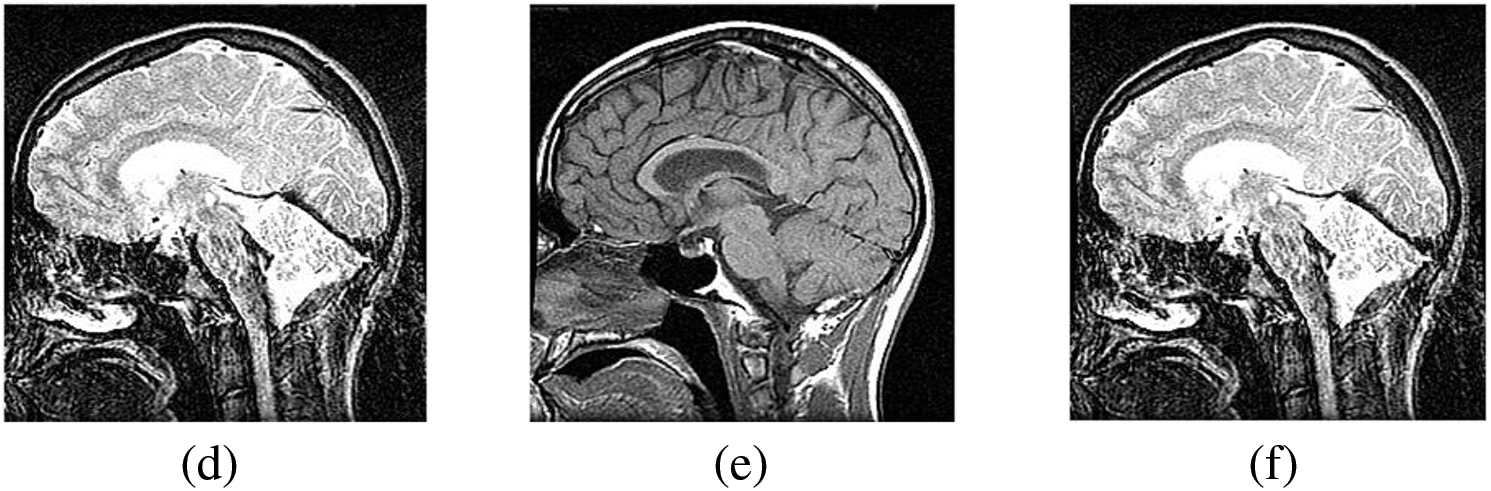

Figs. 4–11 display the original CT and MRI images along with their corresponding enhanced images obtained through the proposed sharpening technique, including Unsharp masking and LF+DFT Sharpen. The enhanced images effectively highlight and enhance minor details, making them clearer and more perceptible. These enhanced images play a crucial role in subsequent stages of the fusion process, where the aim is to integrate the essential information from both CT and MRI modalities.

Figure 7: The sharpened results of “Brain CT and MRI Image set 2” (a), (b) are two source images CT and MRI, respectively, (c), (d) are sharpen images by Unsharp masking and (e), (f) LF+DFT sharpened images

Figs. 4–11 present the fused images obtained from both existing and proposed hybrid approaches. The existing approaches, including PCA, MF, DWT, DTCWT, DCHWT and SWT, initially fuse the source images. Then, the SWT method is combined with the proposed sharpening techniques and applied to fuse the sharpened images. Comparatively, the fused images generated by the proposed methods, namely SWT+Unsharp masking and SWT+(LF+DFT), exhibit significant improvements compared to the baseline techniques. To highlight the differences among the fused images and facilitate a better understanding of the enhanced and informative nature of the images, specific areas are marked with red and green boxes in Figs. 3–10. Furthermore, a magnified version of the region marked with the red box is provided in Figs. 5 and 9 to further illustrate the qualitative analysis of brain datasets.

Understanding the difference between simple and sharpened images is crucial. Sharpened images exhibit higher acutance, which is a subjective measure of edge contrast. Acutance cannot be quantified directly; it relies on the observer’s perception of whether an edge has sufficient contrast or not. Our visual system tends to perceive edges with higher contrast as having more clearly defined boundaries. In Fig. 6, we zoom in on specific areas of the images, highlighting them with green and red boxes for simple and sharpened images, respectively. This allows us to easily observe the dissimilarity between the two versions, particularly in the enhanced details visible within the green boxes.